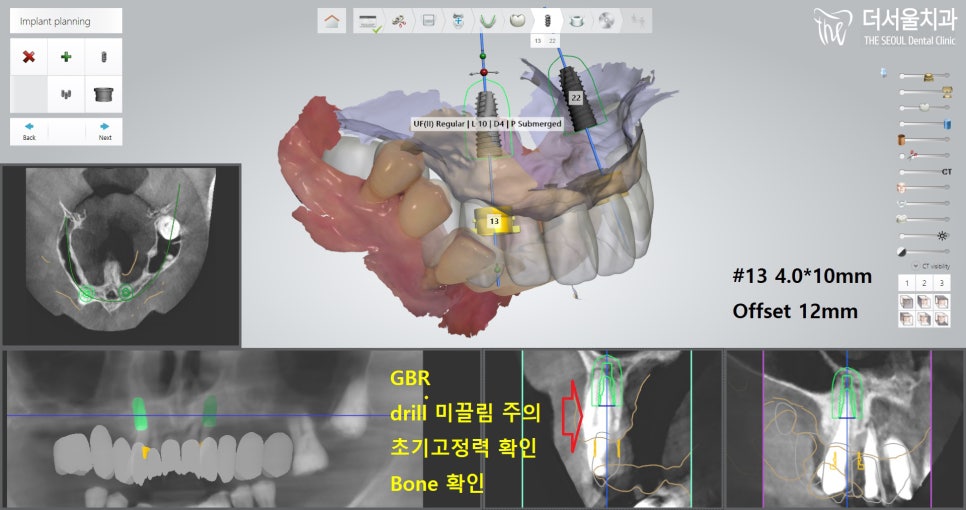

3. 수술 계획 수립 과정

먼저 환자분께 부담이 가지 않게끔

최소 절개를 통하여 진행할 수 있는

가이드 제작에 들어갔습니다.

원래 13번은 발치 계획에 없었으나,

상태가 그렇게 좋지 않았기에

제거하기로 결정을 내렸습니다.

그래서 13번과 22번 위치에 픽스처를 심고,

둘을 지대치로 이용하여

브릿지를 연결시켜 사용하기로 합니다.

아래에 검사를 하는 부분에서

보여지는 것처럼

뼈 상태가 너무 좋지 않기에,

추가적으로 뼈이식을 하기로 합니다.

좀 더 확대해서 보면,

이렇게 픽스처가 골폭을 벗어나있죠?

이러면 제대로 고정되지 않습니다.

결국, 실패로 이어지기에

뼈이식을 해야 되었죠.